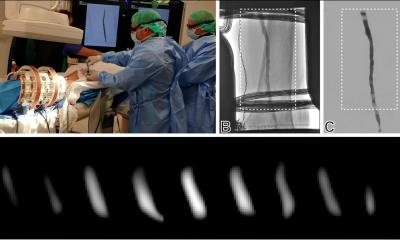

In den fokussierten Röntgenstrahl brachten die Wissenschaftler optische Gitter ein und konnten so zusätzlich zur Absorption der Röntgenstrahlen auch kleinste Phasenverschiebungen und Streuungen der Strahlen an der Probe messen. Die erste Phasenkonstrast-Tomografie an einer kompakten Synchrotronquelle war gelungen.

Die mit der neuen Technik gewonnenen Phasenkontrast-, Dunkelfeld- und Absorptionsbilder ergänzen sich gegenseitig. Flüssigkeiten und Gewebe, die im Absorptionsbild klassischer Röntgenröhren nicht unterscheidbar und damit unsichtbar sind, kommen so plötzlich zum Vorschein. Der durch die neue Röntgentechnik stark verbesserte Weichteilkontrast könnte zudem helfen Tumore früher zu erkennen oder eine schnelle Diagnose – beispielsweise in einem medizinischen Notfall – zu ermöglichen.

Wie trennscharf die neue Technik ist, zeigt sich beim Vergleich von weißem und braunem Fettgewebe. „In einer Maus konnten wir nicht nur Herz, Leber und andere Organe sehr viel besser erkennen sondern sogar weißes von braunem Körperfett unterscheiden“, sagt Eggl.